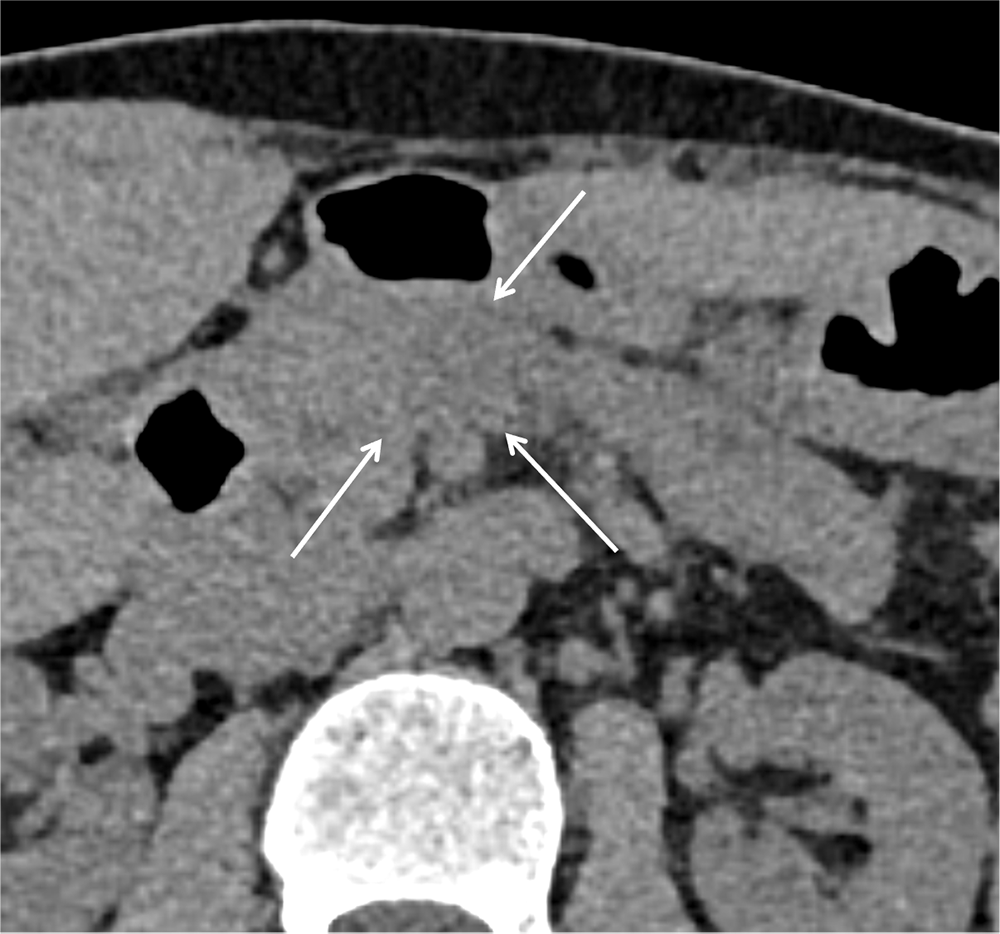

本症例では、腫瘤形成以外に尾側の主膵管拡張を認めたため、単純CTでも病変の存在を指摘することは可能であったが、通常膵癌は単純CTでは正常膵実質と等吸収を呈するため、特に小径の膵癌の場合は随伴する主膵管拡張などの所見がはっきりしない場合もあり、指摘困難な場合がある。典型的な膵癌のDynamic CTでの造影パターンは、病変が最も明瞭となる膵実質相では周囲膵実質と比較して相対的に低吸収で、漸増性に造影され、遅延相では相対的に等~軽度高吸収を呈する。しかし、小径の膵癌(3cm以下)の場合は、膵実質相や門脈相で低吸収を呈さず、遅延相で高吸収として描出される傾向にあると言われており(2)、注意を要す。Dynamic CTは、正常膵実質と腫瘤部とのコントラストを得ることで病変の検出が容易となり、形状や造影パターンなどを評価することで他の膵病変と膵癌との鑑別にも有用である。また、局所進展度の評価にも有用で、膵癌の診断や治療方針決定に重要な役割を担う。

さらにthinスライスのCT画像、MPR(multi-planar reconstruction)、Dual-energy CTを用いた低エネルギーレベルの仮想単色X線画像やIodine mapの併用で、検出能向上や病期診断の精度向上につながると考えられる。Iodine mapは、Dual energy CTのデータからヨード造影剤を抽出して画像化したもので、ヨード濃度とその分布を把握することができる。本症例でも、Iodine mapでは病変と周囲膵実質のヨード濃度の差がわかりやすく、病変をより認識しやすくなった。また、MPR像を用いることで、通常の水平断面像と比べて、病変と主膵管との位置関係の把握が容易となった。